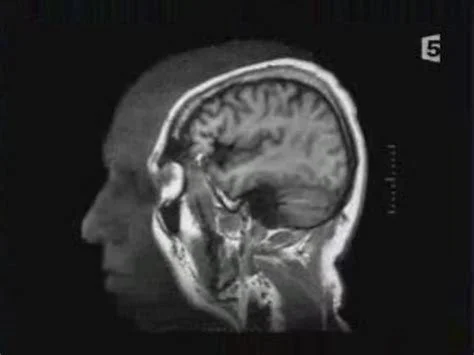

La grande histoire du cerveauLe cerveau, le plus mystérieux des organes humains, est devenu l'eldorado des scientifiques du XXIe siècle. Dans ce film où interviennent des chercheurs du monde entier, un étudiant joue les candides pour évoquer les étapes qui ont jalonné son histoire avant de s'intéresser aux découvertes les plus récentes.